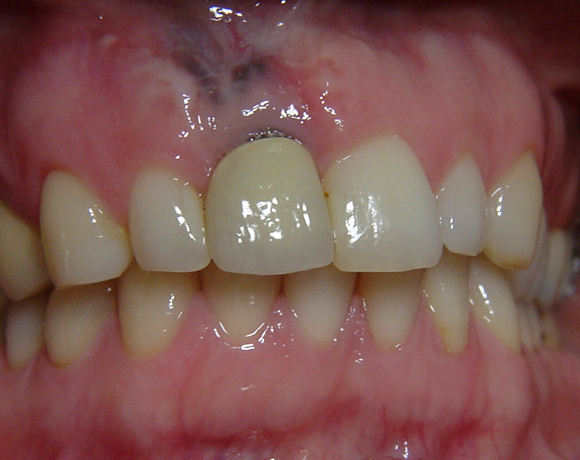

Der vorliegende Patientenfall war noch mit einem Prototypen eines vollkeramischen Aufbaus versorgt worden. Deutlich sichtbar der dunkle Rand an der VMK – Krone der metallkeramischen Versorgung. Die dunkle Verfärbung der Gingiva ist durch ein Amalgamtätoo bedingt.